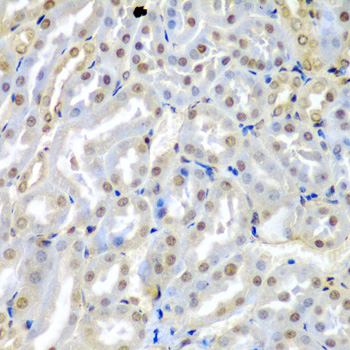

Immunohistochemistry of paraffin-embedded mouse kidney using TUSC2 antibody.

Immunohistochemistry of paraffin-embedded mouse heart using TUSC2 antibody.